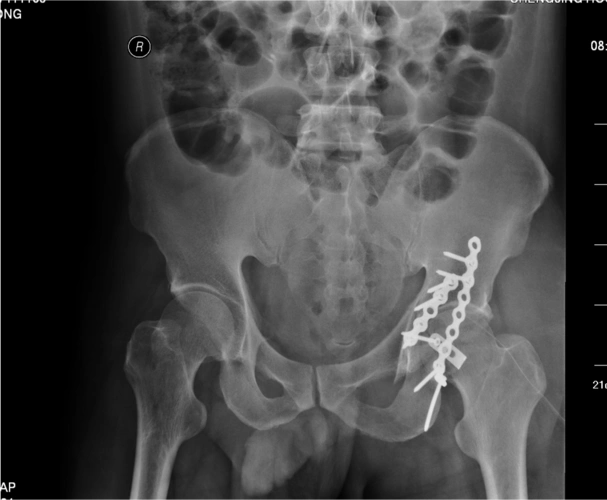

左髋臼骨折(后壁骨折)